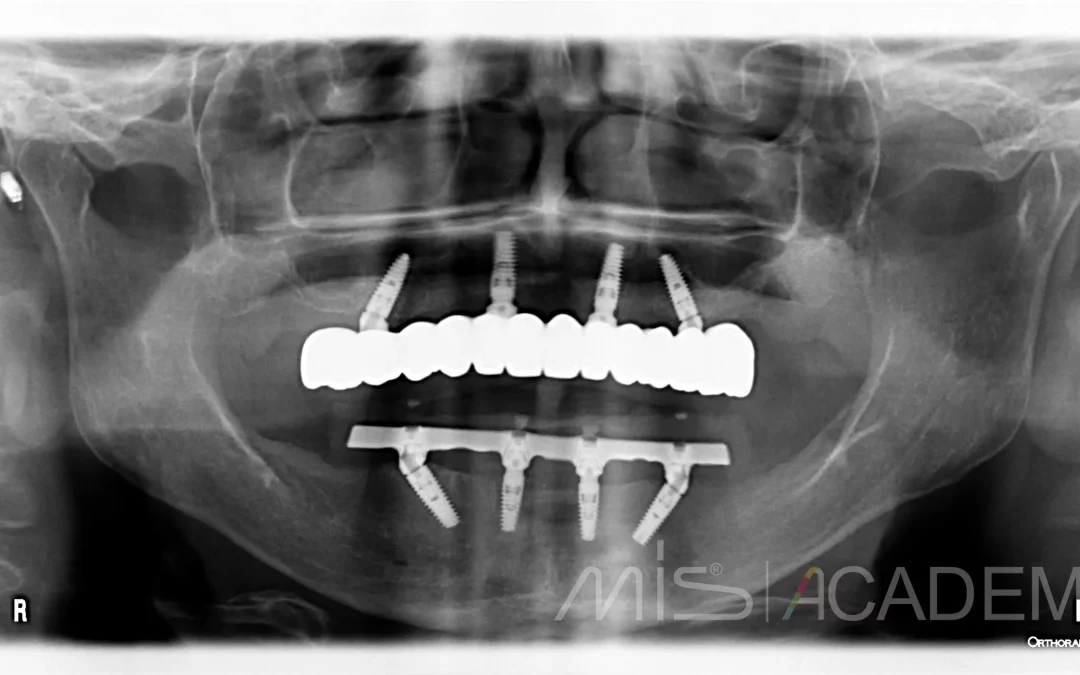

💢 Василий Бочаров г. Владивосток. Продолжение кейса: https://t.me/misrussia/6399 Установили по 4 имплантата на верхней и нижней челюсти и провели немедленную нагрузку металлопластмассовыми конструкциями....

Тотальное восстановление зубного ряда Установили по 4 имплантата на верхней и нижней челюсти и провели немедленную нагрузку металлопластмассовыми конструкциями. После интеграции изготовили постоянные...